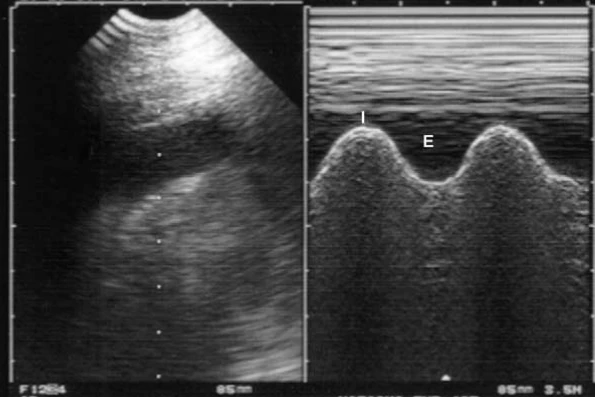

L’image de gauche montre une vue intercostale avec une sonde abdominale convexe (tu noteras que le « bat sign », indispensable pour identifier le ligne pleurale et interpréter correctement les images, n’est pas franc). La zone anéchogène est évocatrice d’une épanchement pleural mais ne permet pas de la confirmer.

L’image de droite montre la même vue en mode TM (ligne de tir indiquée sur l’image de gauche). L’excursion centrifuge inspiratoire de la surface pulmonaire est clairement mise en évidence par le signe de la « sinusoïde », un signe spécifique d’épanchement pleural et un signe attestant par ailleurs d’une bonne fluidité (I, inspiration, E, expiration).